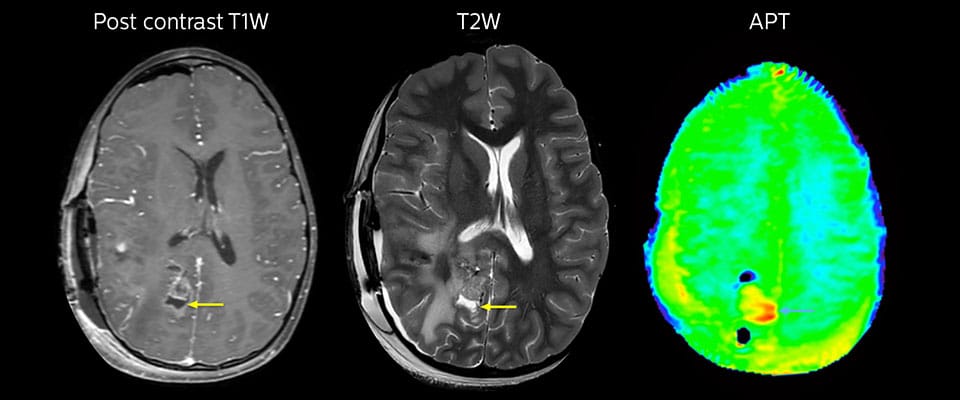

Grosse metastatische Hirnläsion

Diese 10-jährige Patientin unterzog sich vor 7 Jahren der Resektion eines Ewing-Sarkoms, doch jetzt wurde eine grosse metastatische Läsion im Gehirn entdeckt. Diese Läsion zeigt deutlich ein erhöhtes APT-Signal.

MRT mit APT nach der Resektion

Unmittelbar nach der Resektion wurde erneut eine MRT durchgeführt. Die T2-gewichteten und kontrastverstärkten T1-gewichteten Bilder lassen keine eindeutige Unterscheidung von Residualtumorgewebe und postoperativen Gewebeveränderungen zu. Auf dem APT-Bild ist noch ein hohes Signal zu sehen, das auf Residualtumorgewebe hindeuten würde.

Nachuntersuchung im Laufe der Zeit

In späteren Nachuntersuchungsscans weisen die kontrastverstärkten T1-gewichteten Bilder auf rezidivierendes Tumorwachstum hin. Daher wäre es interessant, den prädiktiven Wert von APT in einer grossen Patientengruppe zu untersuchen.